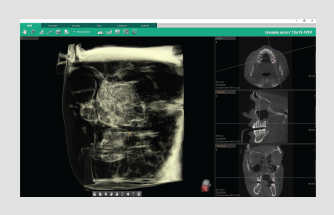

Powered by a new 3D VR graphics engine, the Ez3D-i is the ideal tool to effortlessly obtain the correct perspectives needed for accurate and true-to-measurement diagnosis.

• Various VR coloring modes and 2D filters

Quickly and easily switch between multiple VR views